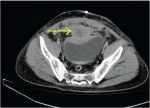

臍尿管囊腫感染致腹痛一例 關(guān)鍵疾?。?a href="http://m.akellydesign.com/tags/so/臍尿管囊腫感染-4-1.html" target="_blank">臍尿管囊腫感染 現(xiàn)病史【一般資料】 女性,49歲,農(nóng)民 【主訴】 下腹痛1月,加重2天 【現(xiàn)病史】患者于1月前無明顯誘因突然出現(xiàn)腹部疼痛不適,以下腹部為重,伴惡心,未嘔吐,呈陣發(fā)性脹痛,并逐漸加重,無發(fā)熱,無咳嗽、咳痰,無胸悶、心悸,無腹瀉,無尿急、尿頻、尿痛,無腰背部反射痛,在當(dāng)?shù)亻g斷輸液治療,效果一般,2天前腹痛加重,為求進(jìn)一步診治,急來我院就診,門診檢查后收入院治療。患者自發(fā)病以來休息差,精神差,未進(jìn)食,大小便正常。 【既往史】平素健康狀況良好。否認(rèn)高血壓病史,否認(rèn)糖尿病病史,否認(rèn)冠心病病史,否認(rèn)慢性支氣管...

韓***波 | 主治醫(yī)師 外科 泌尿外科 瀏覽:3667